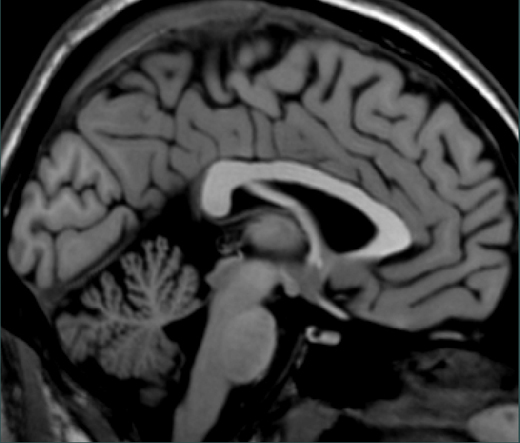

Identify the boundary between the midbrain and the hypothalamus.